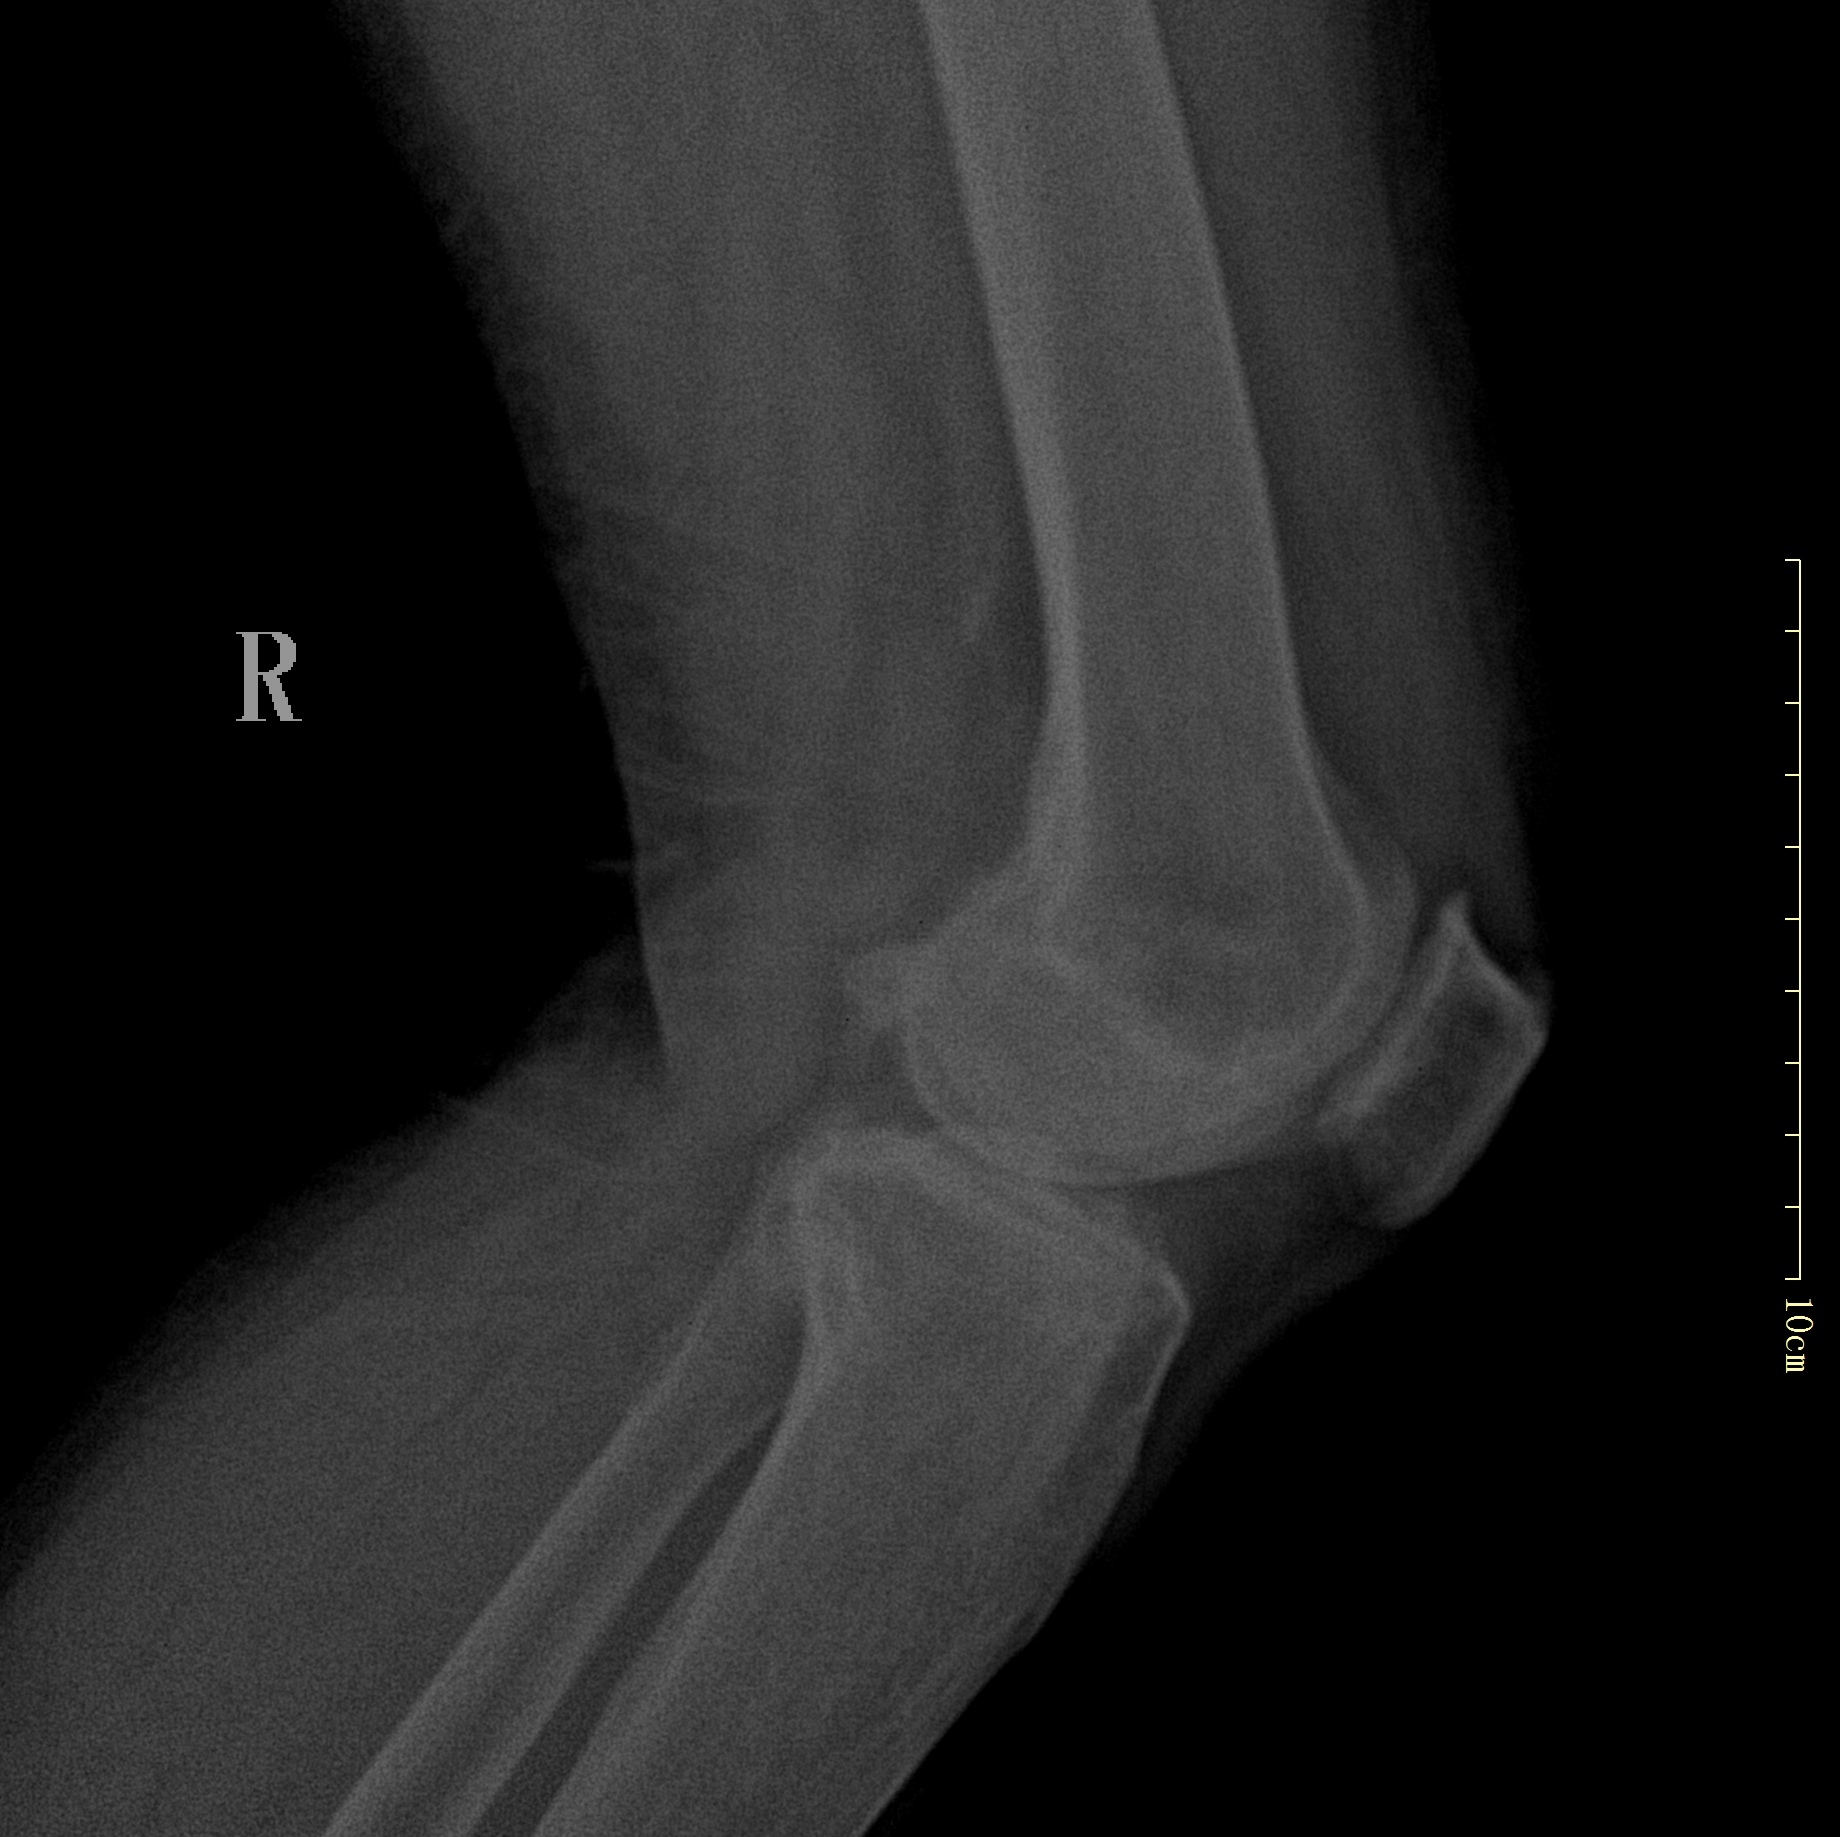

术 前